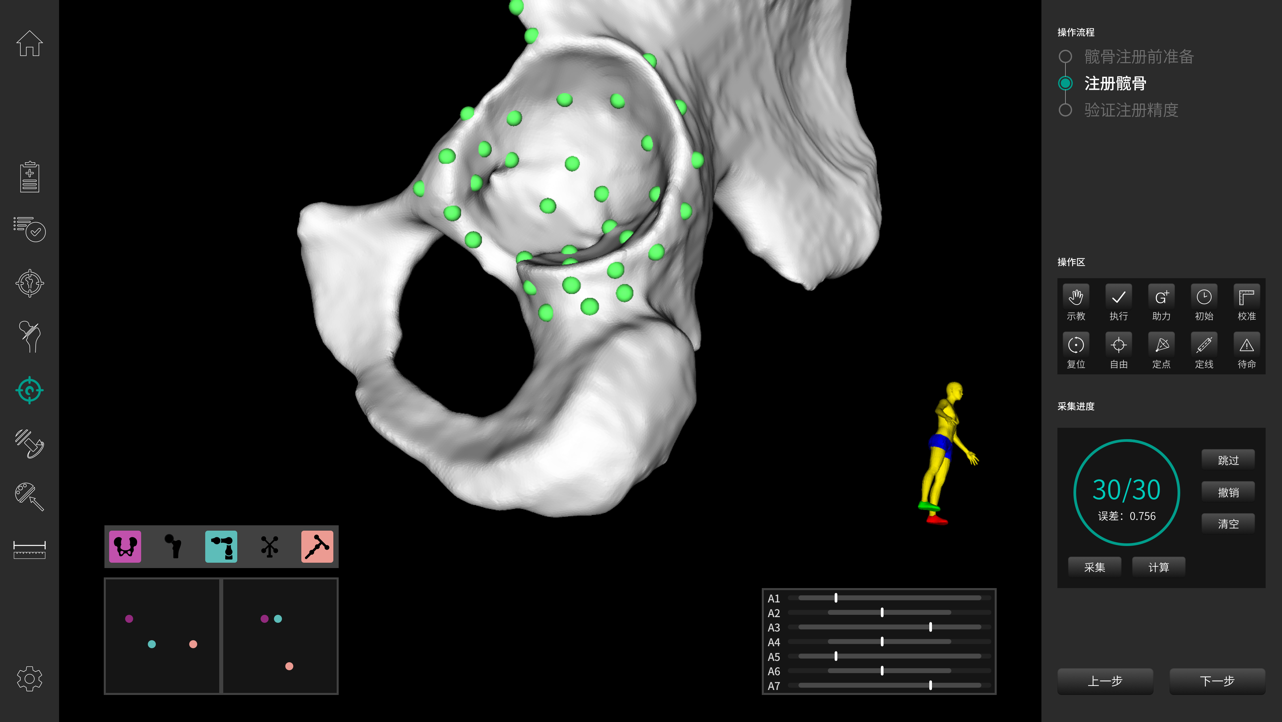

· 注冊精準(zhǔn)穩(wěn)定。

· 穩(wěn)定快速解剖點(diǎn)配準(zhǔn),將術(shù)中生理結(jié)構(gòu)與其術(shù)前影像數(shù)據(jù)建立空間關(guān)聯(lián),保證手術(shù)規(guī)劃的準(zhǔn)確執(zhí)行。配準(zhǔn)時間控制在3-5min。